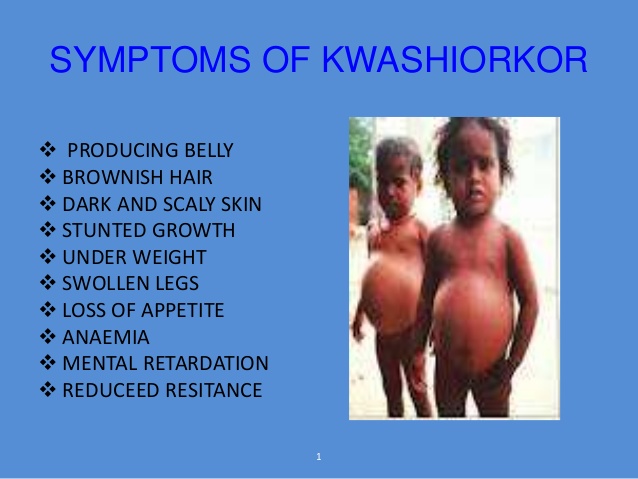

5. NON-COMMUNICABLES DISEASES: These are diseases that CANNOT be passed from person to person but are linked with nutrition or inherited, e.g kwashiorkor, cancer, ulcer, etc.

Child suffering from kwashiorkor

i. Kwashiorkor

5. NON-COMMUNICABLES DISEASES: These are diseases that CANNOT be passed from person to person but are linked with nutrition or inherited, e.g kwashiorkor, cancer, ulcer, etc.

Child suffering from kwashiorkor

i. Kwashiorkor